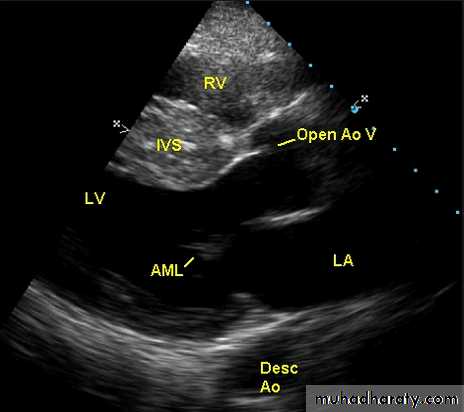

Hypertrophic cardiomyopathyThis is the most common form of cardiomyopathyGenetic disorder, usually with autosomal dominant transmission

The hypertrophy may be generalised or confined largely to the interventricular septum (asymmetric septal hypertrophy) or other regions (e.g. apical hypertrophic cardiomyopathy)

Dynamic LV outflow tract obstruction ( atleast >30 mm, usually > 50mm Hg)

ECHO Echocardiography is diagnostic